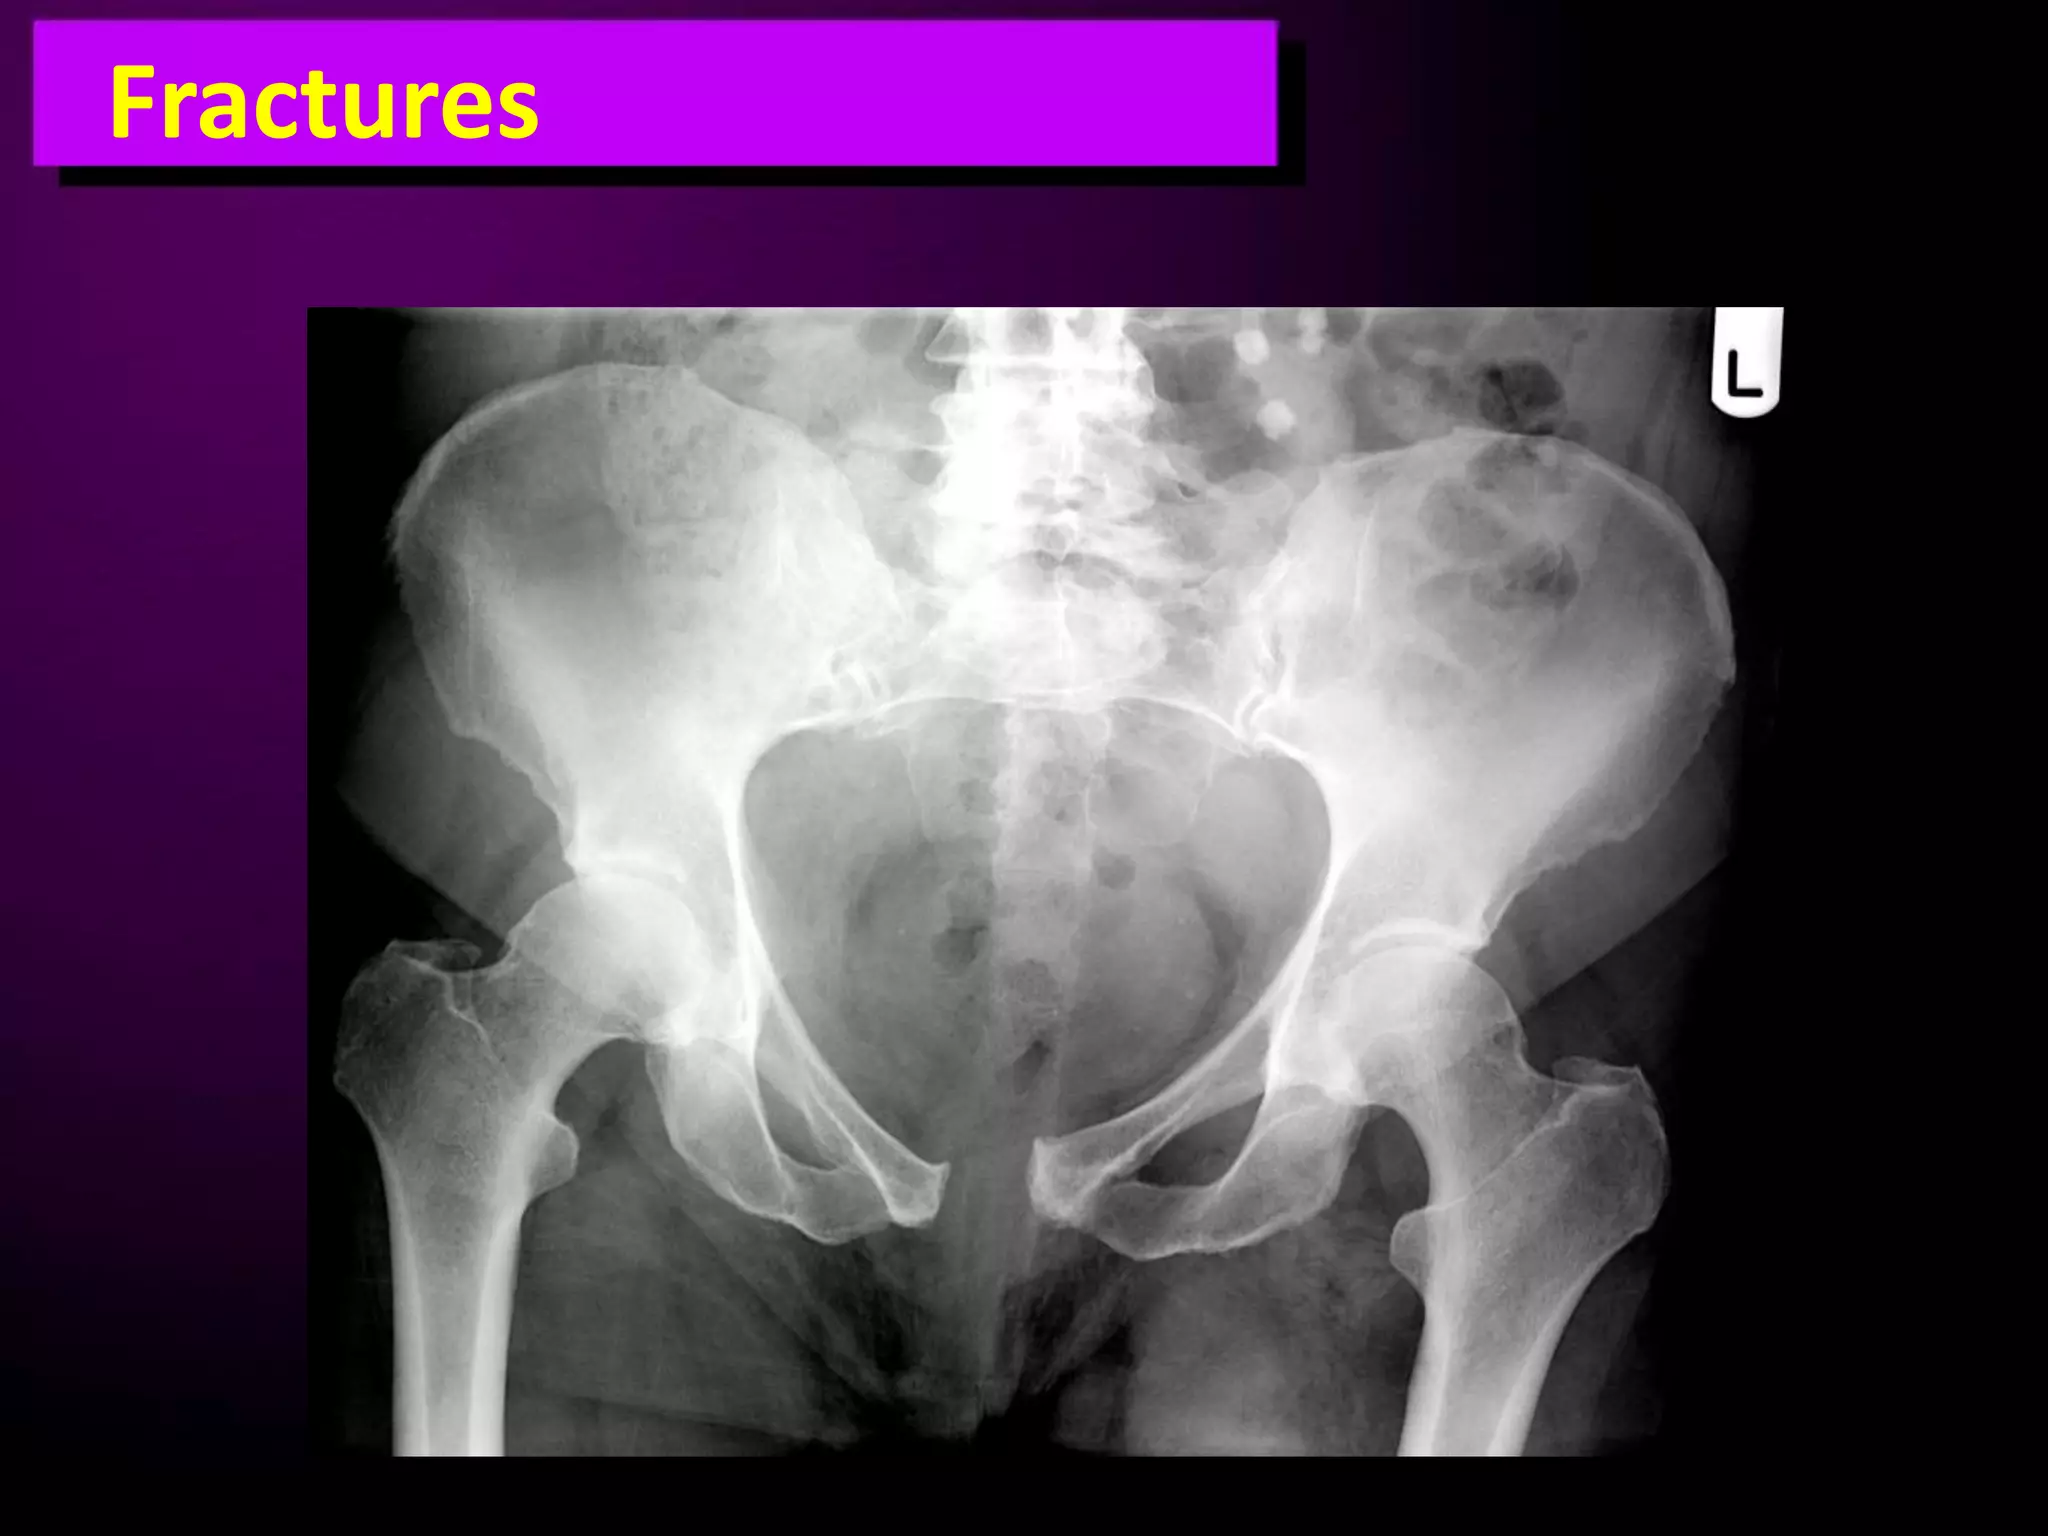

This document discusses trauma to the pelvis, hips, knees, ankles, and feet. It covers anatomy, imaging techniques, and types of fractures and dislocations that can occur in these areas. The types of fractures discussed include pelvic ring fractures, acetabular fractures, and fractures of the femur, tibia, fibula, and bones of the foot. Imaging views used include AP, inlet, and outlet views of the pelvis. Dislocations and fractures of the knee, ankle, and foot joints are also examined.